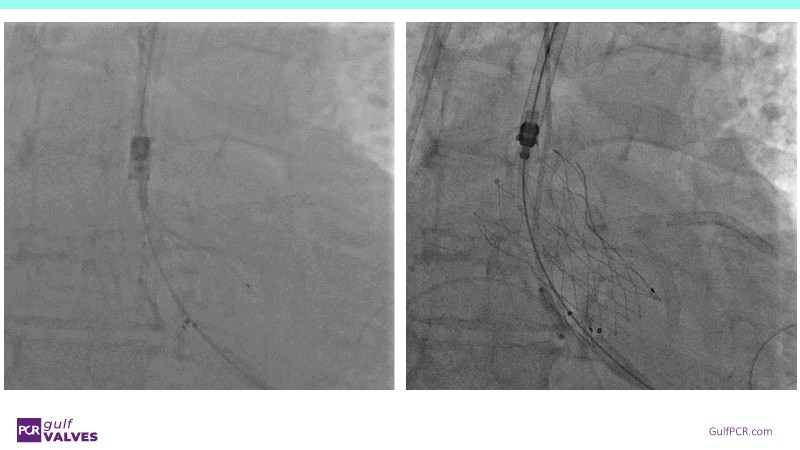

Discover a selection of cases showcasing the key features of the Navitor Valve System and its clinical applications. This session explores auxiliary access, the use of Navitor in alternative access and complex PCI, its performance in challenging peripheral anatomies, and innovative outcomes with the Vantage 30D system.